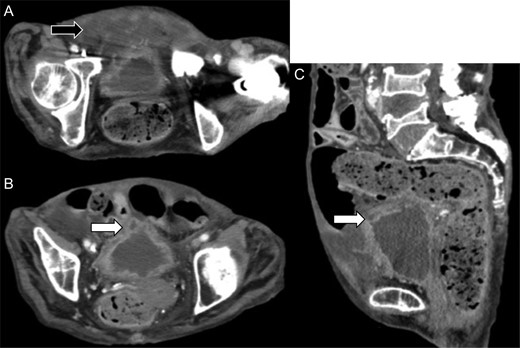

She was given an antibiotic (meropenem 0.5 g, every 8 h), but the next day, the abdominal pain worsened. Laboratory test showed elevation of the inflammation reaction values, and enhanced CT showed free air in the abdominal cavity (Fig. 2A), with increased fluid collection in the anterior space of the bladder (Fig. 2B). We performed emergency laparotomy for suspicion of digestive tract perforation. There was a small hole at the dome of the urinary bladder and another at the peritoneum, and very thick pus extruded into the abdominal cavity. We opened the front part of the urinary bladder, sutured the hole and sutured the bladder to close it. A permanent urinary catheter was placed for bladder drainage and decompression. The postoperative course was uneventful, and the inflammation reaction improved. She was discharged on the 21st postoperative day and had no recurrence since then.

Enhanced abdominal computed tomography 1 day after admission showing (A) free air in the abdominal cavity (white arrow) and (B) massive fluid collection in the posterior space of the urinary bladder (black arrow).